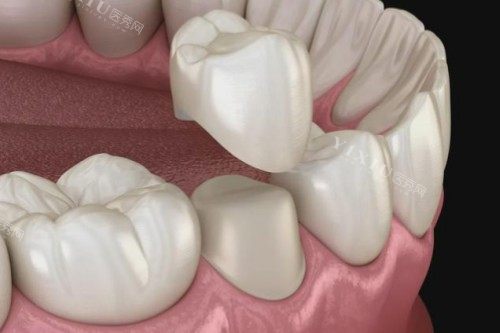

南京雅康口腔作为栖霞区正规的镶牙医院,拥有可靠的医疗团队和靠前的诊疗设备。医院采用国内外标准的消毒流程,确保治疗安心。雅康口腔的镶牙技术涵盖多种修复方式,包括烤瓷牙、全瓷牙、活动义齿等,能够满足不同患者的需求。

医院特别看重个性化治疗方案设计,医生会根据患者口腔状况、咬合关系等因素,制定较适合的修复方案。雅康口腔的医生团队经验充足,在复杂病例处理上表现出色,尤其擅长前牙美学修复,能够实现自然美观的结果。

医院特别重视患者的舒适体验,从初诊检查到较终修复完成,全程采用不痛技术。雅丰瑞齿固德口腔的烤瓷牙修复采用优质材料,色泽自然,耐用度高。医院还提供完善的售后服务,定期回访患者,确保修复结果持久稳定。

睿白口腔以其过关的镶牙技术在栖霞区赢得了良好声誉。医院拥有独立的义齿加工中心,能够比较准把控修复体的制作质量。睿白口腔特别看重咬合重建技术,在修养牙齿功能的同时,确保患者获得舒适的咬合体验。

医院的医生团队定期参加国内外学术交流,掌握较新的镶牙技术。睿白口腔的全瓷牙修复技术尤为出色,采用CAD/CAM智能化设计制作,精度高,美观度好。对于复杂的全口义齿修复,医院也有独到的技术优势。